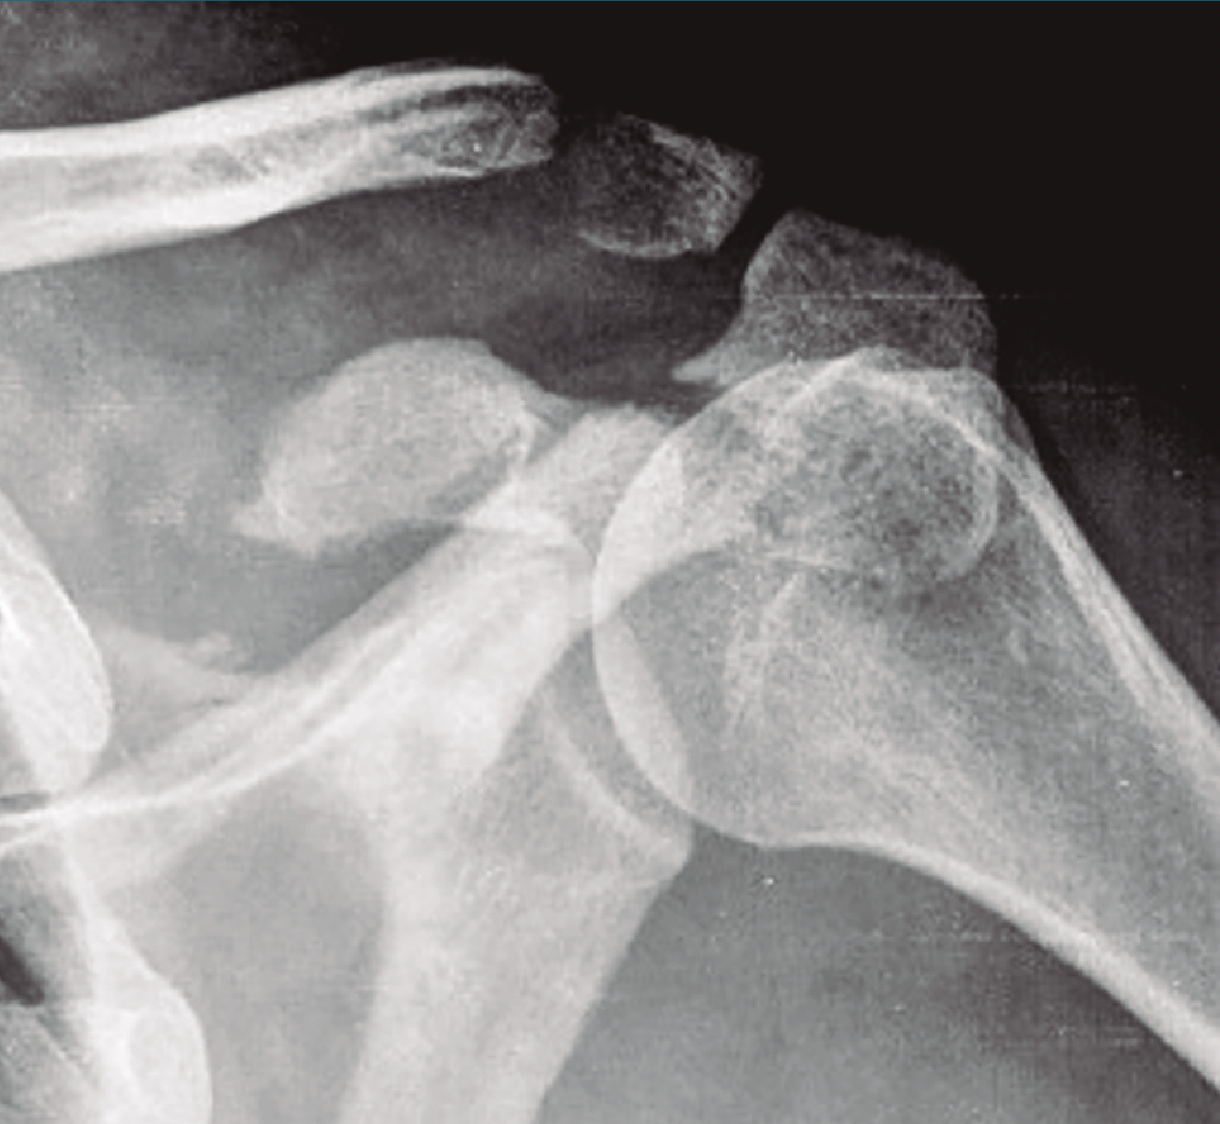

Existen distintos tipos de fracturas escapulares. En ocasiones, tras una fractura glenoidea (35%) (Figura 3), pueden producirse fracturas de coracoides (7%) (Figura 4) y también pueden ocurrir fracturas escapulares indirectas por caídas con la mano extendida(1,3,5).

Figura 4. Radiografía simple de fractura de coracoides.